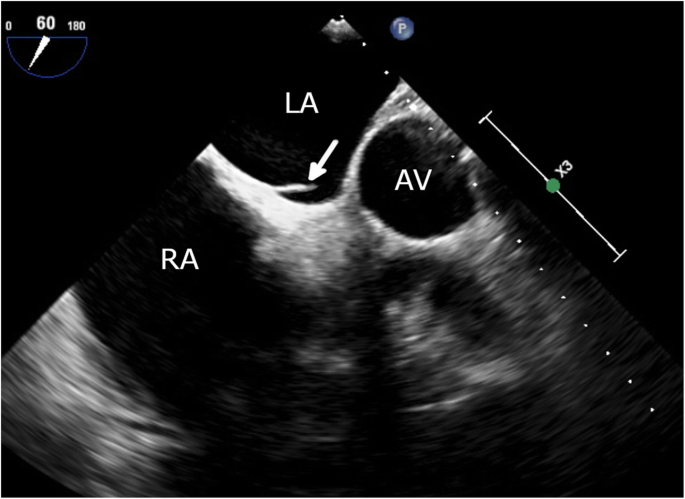

Given the high index of suspicion of an intracavitary thrombus in the setting of new-onset AF and progression of the cyanotic toes, the patient was referred to cardiology, where transesophageal echocardiography (TEE) revealed an anomalous LASP and a 7.7 × 3 mm mobile ovoid echodense mass with a narrow stalk attached to the pouch, suggestive of thrombus (Fig. 4, Supplemental Video 1). There was no evidence of an atrial septal defect on color Doppler flow imaging (Fig. 5), although it showed mild mitral regurgitation. A further confirmatory agitated saline test to exclude atrial septal defect was not performed to avoid dislodging the thrombus. No mass was seen in the left atrial appendage (LAA; peak emptying velocity 63 cm/s). Three-dimensional (3D) TEE visualized the LASP containing a mobile thrombus with attachment of its stalk to the interatrial septum (Fig. 6 and Supplemental Video 2). It is noteworthy that the exact shape and volume of the mass were revealed by the 3D acquisition.

Transesophageal echocardiogram (TEE) showing LASP opening into the left atrial (LA) cavity and a 7.7 × 3 mm thrombus (arrow), with the site of attachment corresponding to the LASP (2-dimensional TEE images at 60° [a] and biplane TEE image [b] of the interatrial septum). AV, aortic valve; LA, left atrium; RA, right atrium